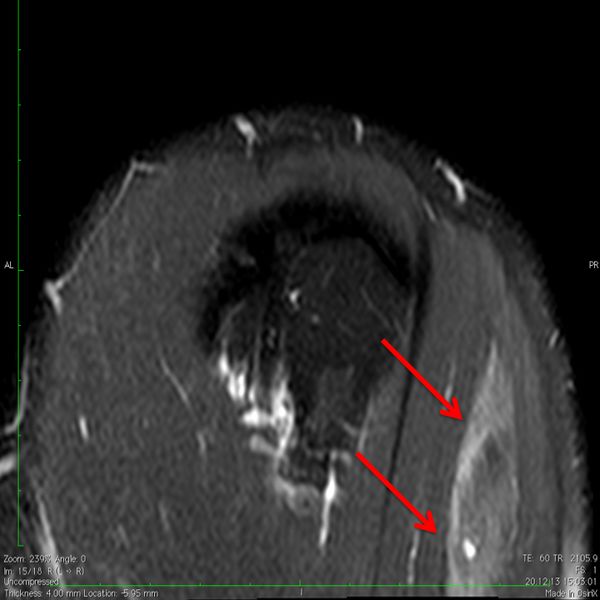

Deltoid insertion disruption following trauma